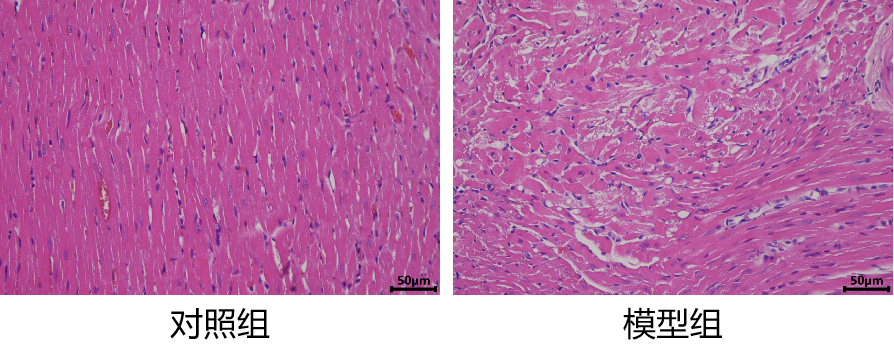

二、小鼠慢性心衰模型

造模:C57bl/6J小鼠麻醉后,在胸骨上缘下方处,横向剪开一个开口。在胸骨上缘下方处,横向剪开一个开口。使用缝合线穿过主动脉弓部,连同垫针将主动脉弓部结扎,然后拔出垫针。逐层缝合伤口。放入保温箱待小鼠苏醒后放入鼠笼。8周后进行模型验证。

1.造模过程

2.模型验证

左室射血分数EF值低于50%是心衰, 40%-50%:轻度心衰,在30%-40%:中度心衰,如果低于30%属于重度心衰。心脏左室短轴缩短率FS值低于25%,表明左心室缩短率明显降低。